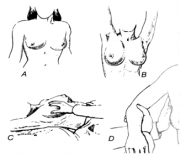

| תאריך | שם | תמונה ממוזערת | גודל | משתמש | תיאור | גרסאות |

|---|---|---|---|---|---|---|

| 18:49, 31 באוגוסט 2012 | Breast1612.png (קובץ) |  |

214 קילו־בייטים | Motyk | 1 | |

| 18:47, 31 באוגוסט 2012 | Breast412b.png (קובץ) |  |

451 קילו־בייטים | Motyk | 1 | |

| 18:46, 31 באוגוסט 2012 | Breast412c.png (קובץ) |  |

300 קילו־בייטים | Motyk | 1 | |

| 10:50, 31 באוגוסט 2012 | Breast412.png (קובץ) |  |

212 קילו־בייטים | Motyk | 1 | |

| 10:46, 31 באוגוסט 2012 | Breast312.png (קובץ) |  |

620 קילו־בייטים | Motyk | 1 | |

| 16:18, 29 באוגוסט 2012 | Breast212.png (קובץ) |  |

119 קילו־בייטים | Motyk | 1 | |